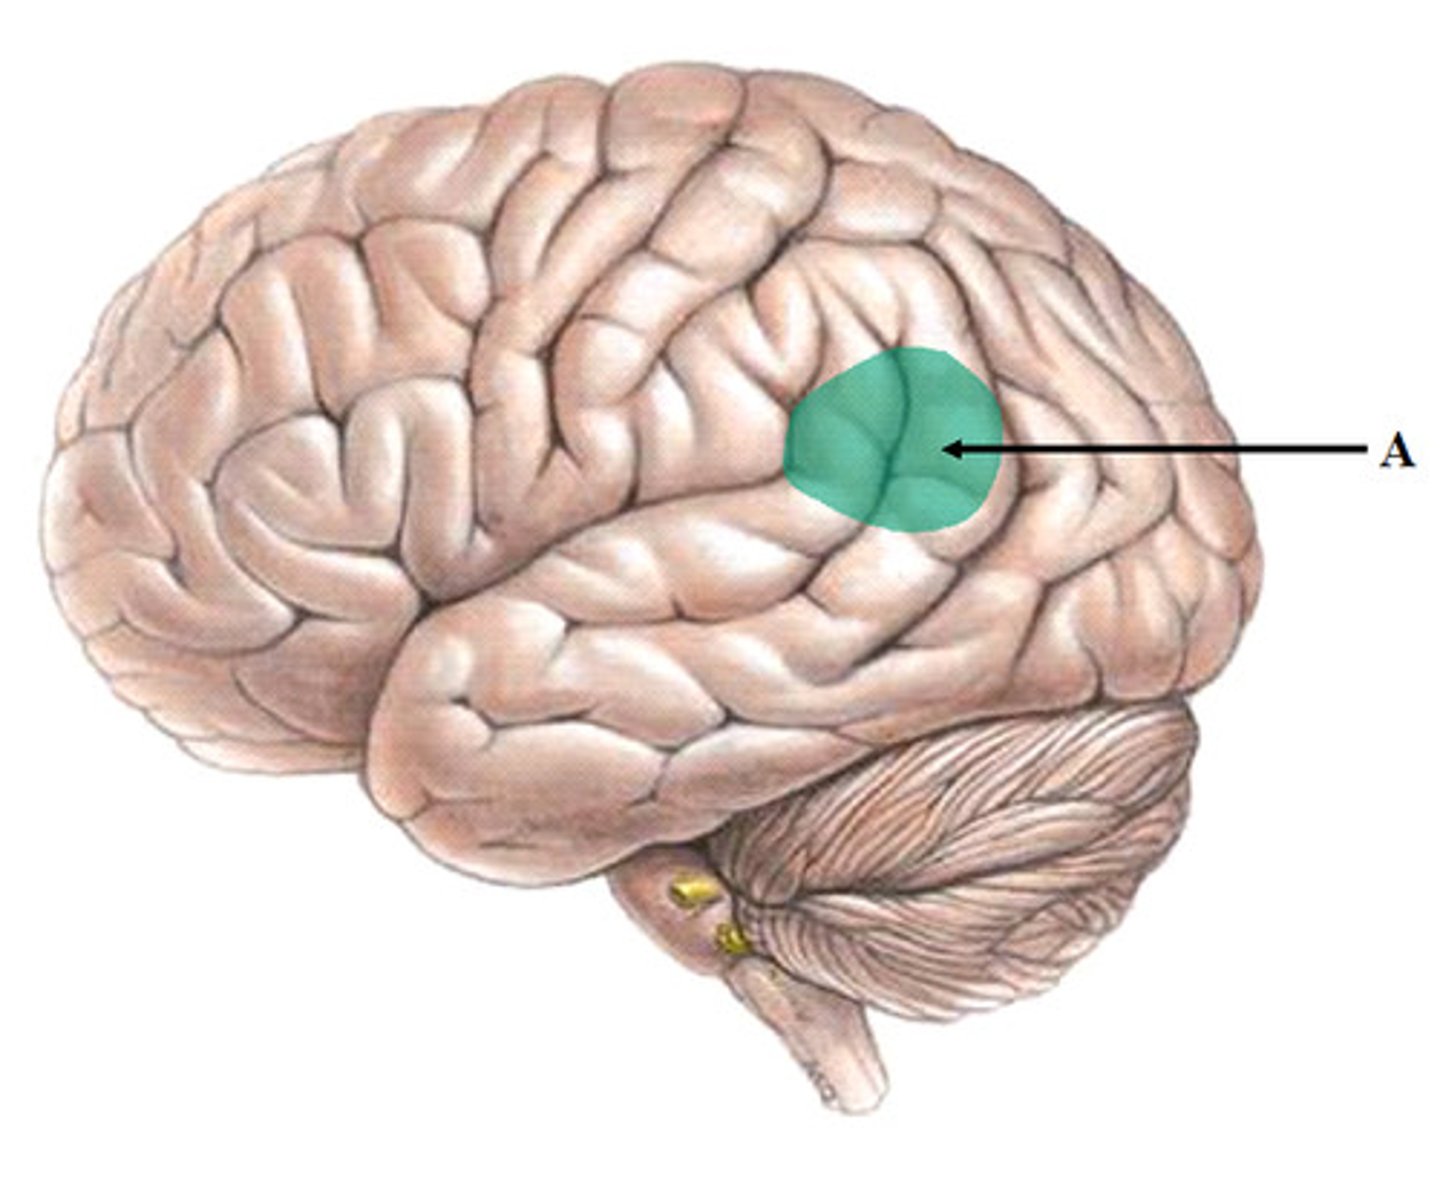

Wernicke's area

part of the temporal lobe involved in understanding speech